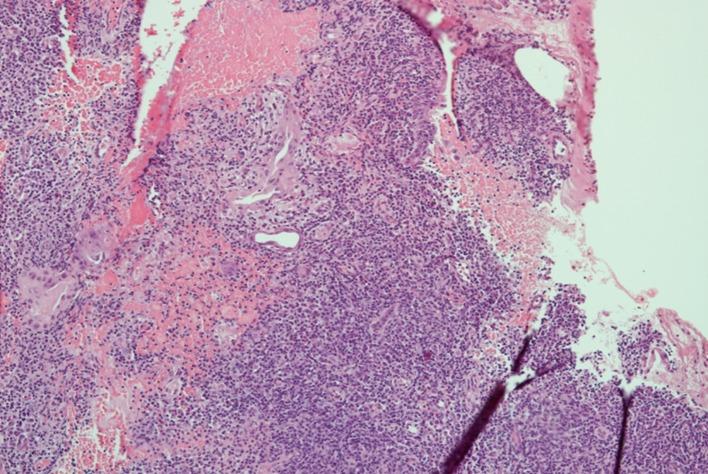

Mucosal leishmaniasis mimicking T-cell lymphoma in a patient receiving monoclonal antibody against TNFα.

PLoS Negl Trop Dis. 2017 Sep 21;11(9):e0005807. doi: 10.1371/journal.pntd.0005807. eCollection 2017 Sep.

DOI:10.1371/journal.pntd.0005807

PMID:28934199